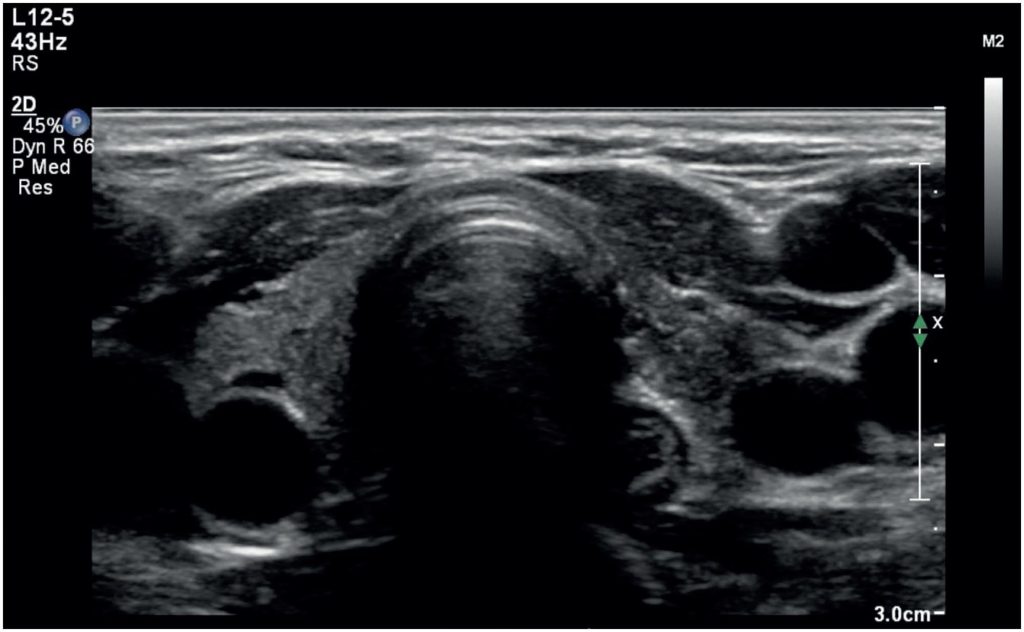

Hypothyroidism is most frequently caused by Hashimoto’s thyroiditis. While thyrotropin receptor antibodies are well-known in Graves’ disease-induced hyperthyroidism, their role in hypothyroidism is emerging. We report the case of a 37-year-old woman with facial and periorbital edema, weight gain, and hoarseness suggestive of hypothyroidism. Elevated thyroid stimulating hormone (TSH; 131mIU/L) and decreased free thyroxine (0.2ng/dL, 2.6pmol/L) levels confirmed this diagnosis. Laboratory findings showed dyslipidemia, impaired renal function, elevated creatine phosphokinase levels, and anemia. Despite negative results for thyroid peroxidase (TPO-Ab) and thyroglobulin (TgAb) antibodies, positive thyrotropin receptor antibodies (11IU/L) suggested an autoimmune etiology. Thyroid ultrasound confirmed atrophic thyroiditis. Levothyroxine treatment improved the symptoms and laboratory values. Two months after diagnosis, the patient became pregnant. Anemia relapsed during pregnancy, thyrotropin receptor antibodies levels normalized, and postpartum follow-up revealed stable thyroid function without affecting the newborn thyroid function. This case underscores the diagnostic challenges of negative TPOAb and TgAb hypothyroidism, which is often misdiagnosed as Hashimoto’s thyroiditis, and highlights the need for functional discrimination in thyrotropin receptor antibodies assays. Thyrotropin receptor antibodies measurements can help in the differential diagnosis of rapidly evolving hypothyroidism in women with negative TPO-Ab and thyrotropin receptor antibodies levels, especially in women of childbearing age. Further research is essential to understand thyrotropin-binding inhibitory immunoglobulin-mediated hypothyroidism and to develop targeted therapies.